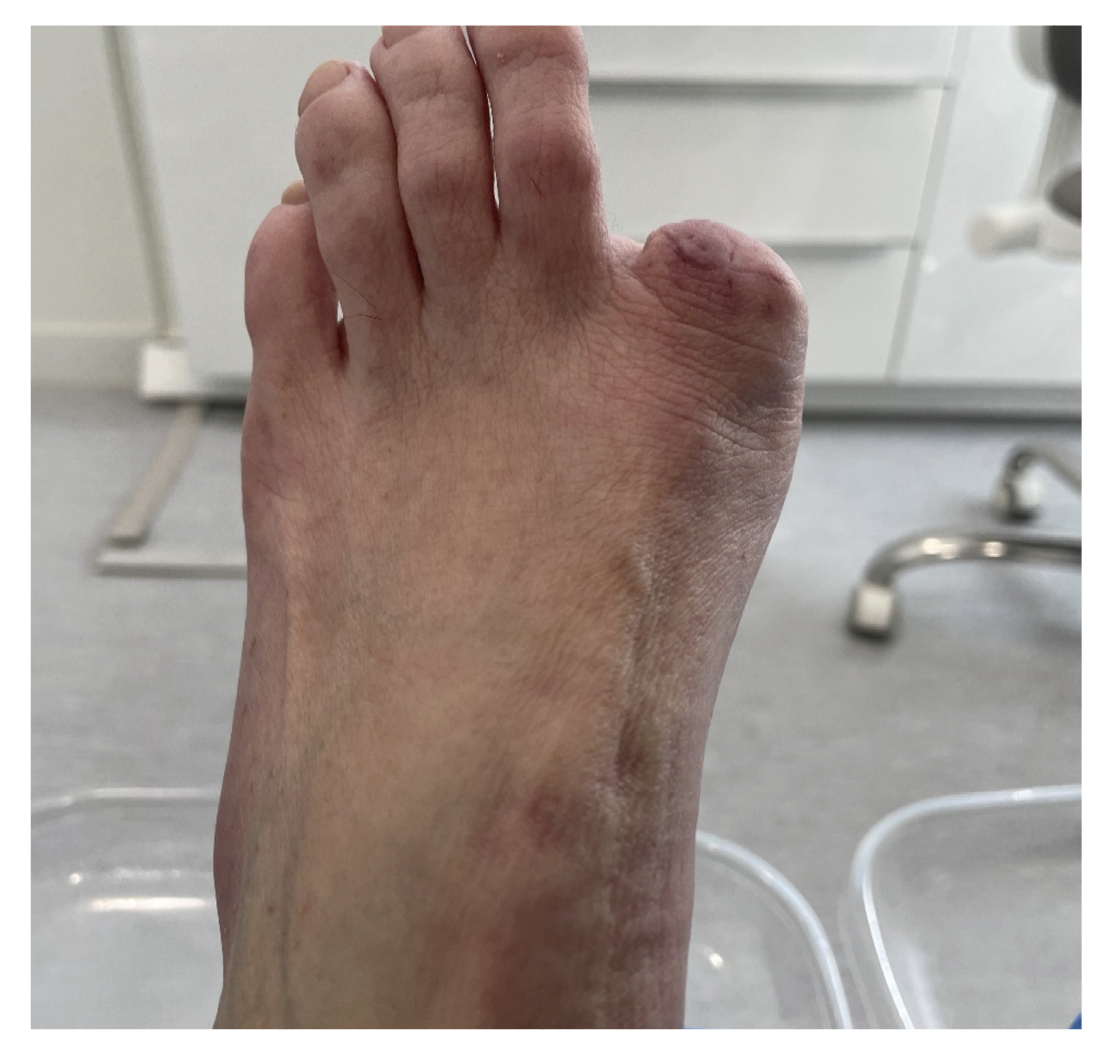

5 days postoperatively, the patient’s first dressing change was performed, which showed a good appearance and no local infection. The patient was explained the result of pathology and referred to the oncology service of her hospital, and from there to the dermatology and plastic surgery service where digital amputation was performed (Figure 10). Subsequent follow-up was conducted by the Oncology service for the next 6 months. After different tests, it was determined that no other treatment was needed. Figure 11 shows the timeline of the clinical case.